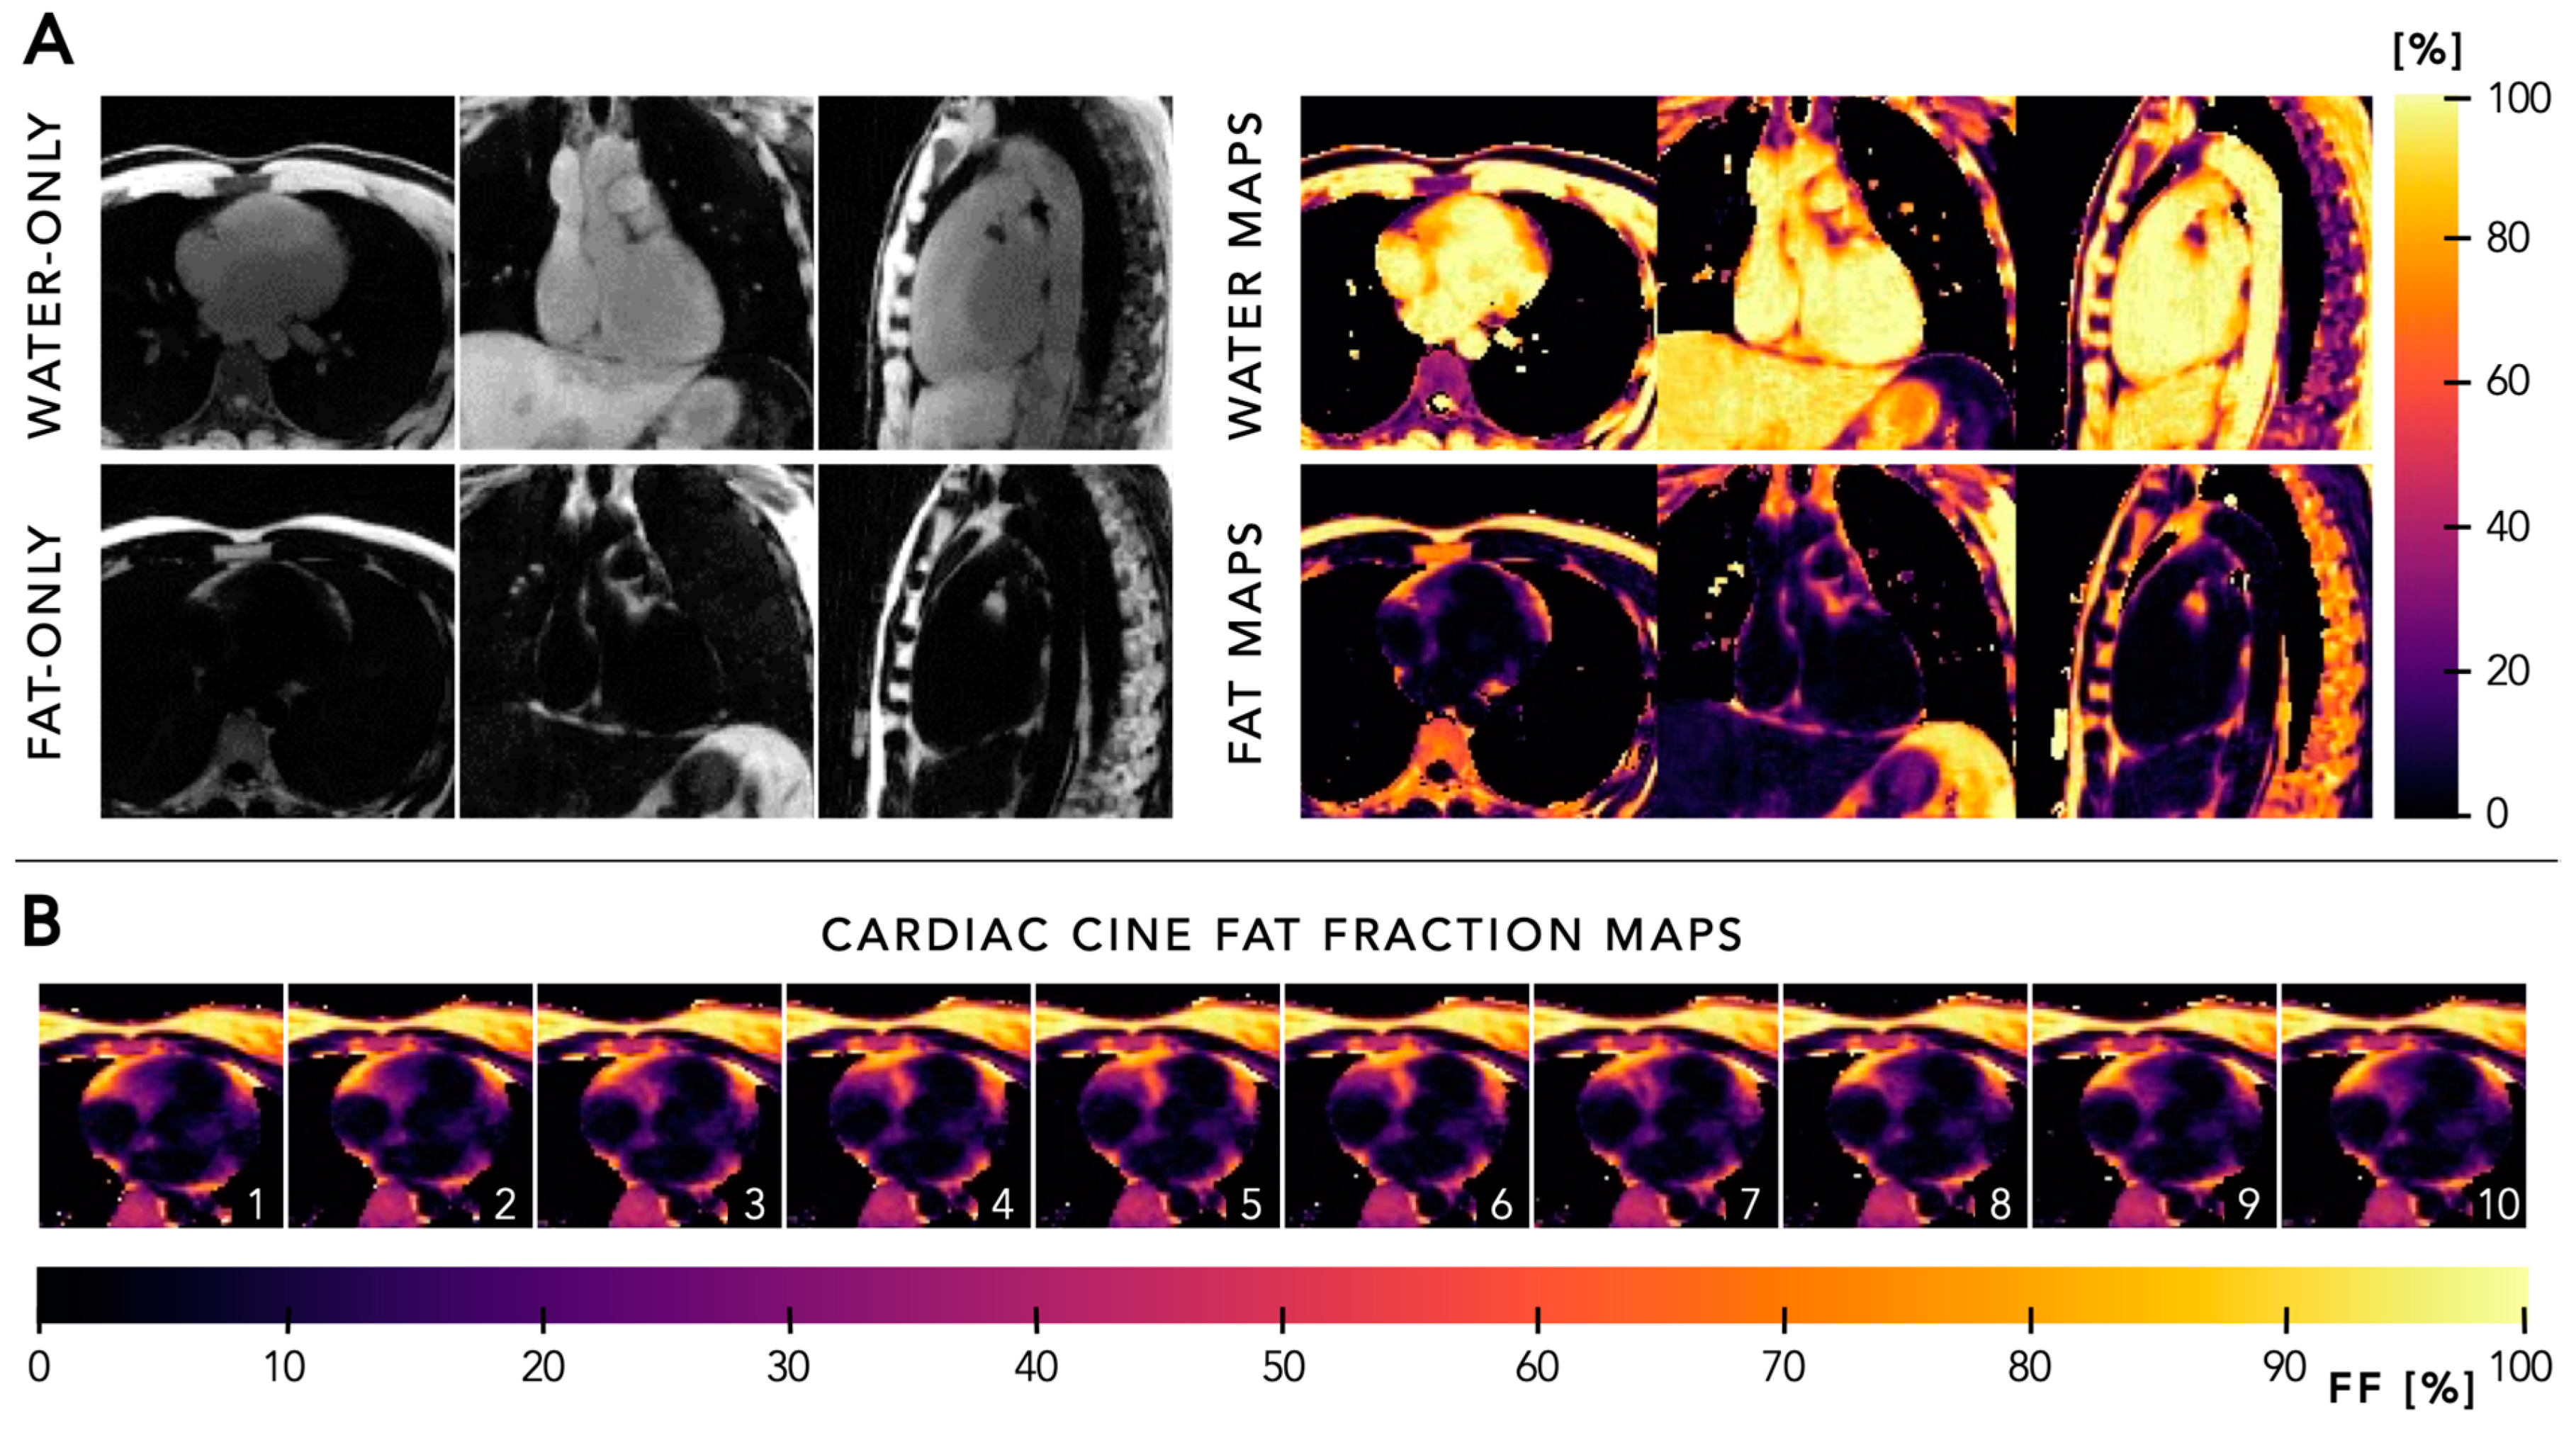

5.4. Quantitative Mapping

6.1. Fat Suppression

- Mackowiak, A.L.C.; Roy, C.W.; Yerly, J.; Falcao, M.B.L.; Bacher, M.; Speier, P.; Piccini, D.; Stuber, M.; Bastiaansen, J.A.M. Motion-resolved fat-fraction mapping with whole-heart free-running multiecho GRE and pilot tone. Magn. Reson. Med. 2023, 90, 922–938. [Google Scholar] [CrossRef] [PubMed]

- Daude, P.; Troalen, T.; Mackowiak, A.L.C.; Royer, E.; Piccini, D.; Yerly, J.; Pfeuffer, J.; Kober, F.; Gouny, S.C.; Bernard, M.; et al. Trajectory correction enables free-running chemical shift encoded imaging for accurate cardiac proton-density fat fraction quantification at 3T. J. Cardiovasc. Magn. Reson. 2024, 26, 101048. [Google Scholar] [CrossRef]